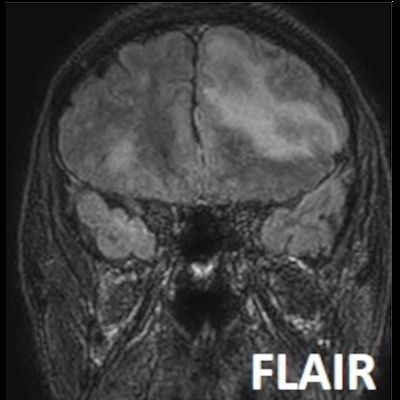

- Bilateral asimetrik subkortikal ve derin beyaz cevherde T1 ağırlıklı görüntülerde belirgin hipointens (oklar), T2A görüntülerde hiperintens (oklar), gri cevhere bakan kesimi düzgün (oklar), DAG’de hiperintens (ok) lezyonlar izlendi. Lezyonlarda T2/FLAIR uyumsuzluğu vardı (ok). Serebellar beyaz cevherde dentat nukleusu koruyan hilal işareti görüldü (ok başı). SWI sekansta sol motor kortekste hipointens kronik glioinflamatuar reaksiyon ile uyumlu sinyal değişikliği izlendi (ok başı).

- Çoğunlukla subkortikal beyaz cevherde ve U fiberlerde, asimetrik, genelde kitle etkisi yapmayan ve kontrastlanmayan demiyelinizan lezyonlar görülür. Korteks ve derin gri cevher tutulumu daha nadirdir.

- PML lezyonları, T1A görüntülerde belirgin hipointenstir. Gri cevhere bakan yüzleri keskin olup T2/FLAIR uyumsuzluğu önemli özelliğidir.

- PML lezyonlarında kronik olarak aktive olan glial hücreler ve mikroglia/makrofajlar sitoplazmalarında yüksek seviyelerde demir ve pigment içerebilir ve SWI da hipointens olarak görülür.